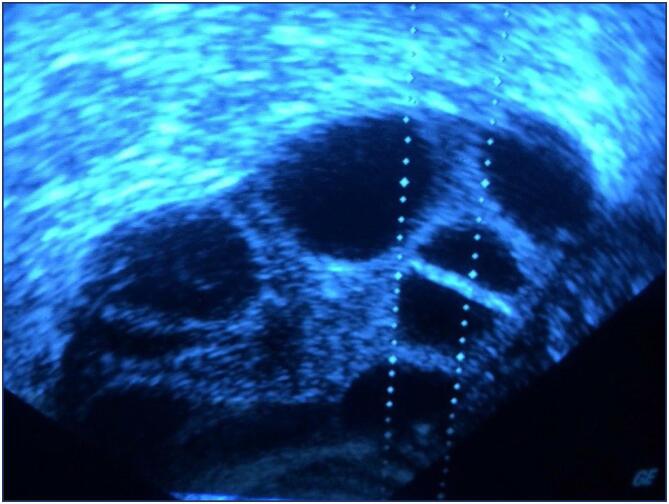

Methods: Before enrolling in the ICSI-ET cycle, participants had their FSH and LH levels assessed on the second day of the cycle. The ovarian degrees of the participants were evaluated by transvaginal ultrasonography. Participants underwent controlled ovarian stimulation using the GnRH antagonist protocol. TV-USG and serial E2 measurements were performed at appropriate intervals to follow follicular development. Follicle sizes, quantity, and endometrial thickness were recorded. Total Antioxidant and Oxidant Status, and Oxidative analyses were conducted using Rel Assay Diagnostics Assay Kits.